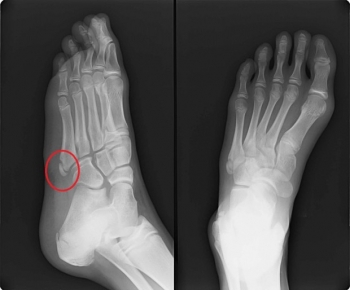

ヒトの中足骨は、左右の足根骨の遠位に5本ずつ存在する細長い管状骨で、趾節骨より長く、内側から外側へ向けて第1 - 第5趾と対応して、第1中足骨、第2中足骨、第3中足骨、第4中足骨、第5中足骨と呼ばれます。

第1中足骨が最も短く、最も太い。第2中足骨が最も長い。第3、第4、第5中足骨の順で短くなる。中足骨は中足骨頭(遠位端)・中足骨底(近位端)・中足骨体(骨幹部)の3つの部分に分けられます。

介達外力では踏み外し時の内がえし外力による短腓骨筋の急激な収縮による第5中足骨基底部剥離骨折(下駄骨折と呼ばれる)が代表的です

第5中足骨近位骨幹部での骨折はジョーンズと呼ばれ、遷延治癒や偽関節になりやすい。